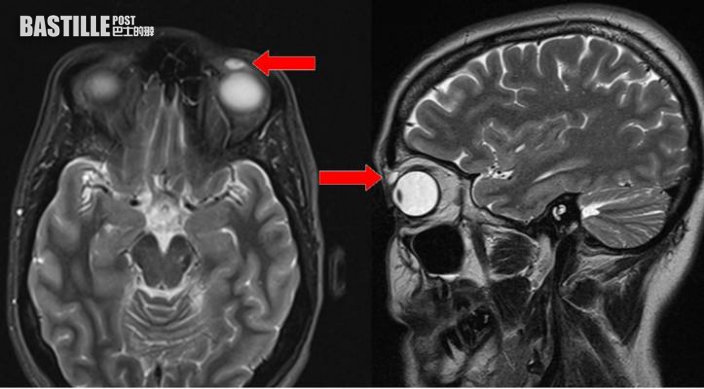

根據《英國醫學期刊》資料顯示,該名英國婦人起初因為左眼持續腫脹且有下垂症狀而求醫,觸碰時更會出現痛楚。醫生經磁力共振(MRI)檢查後竟發現婦人眼內藏有一片約8 mm×4 mm×6 mm的隱形眼鏡,醫生其後替婦人切開囊腫取出隱形眼鏡。